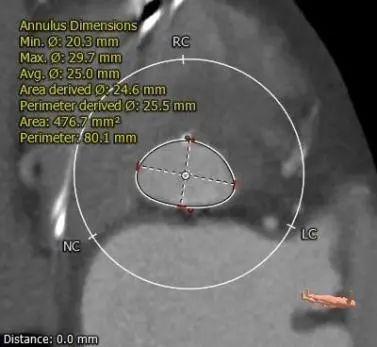

主动脉根部测量

瓣上测量

3.推荐22mm球囊预扩,根据球扩后腰征决定AV26还是AV29瓣膜,瓣环下2mm定位释放,建议释放后调整至右前斜足位 RAO 6 CRA 35 左右进一步确定人工瓣膜展开形态。